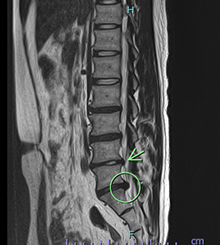

痛みの原因を見るSTIR MRI

腰椎分離症(初期)